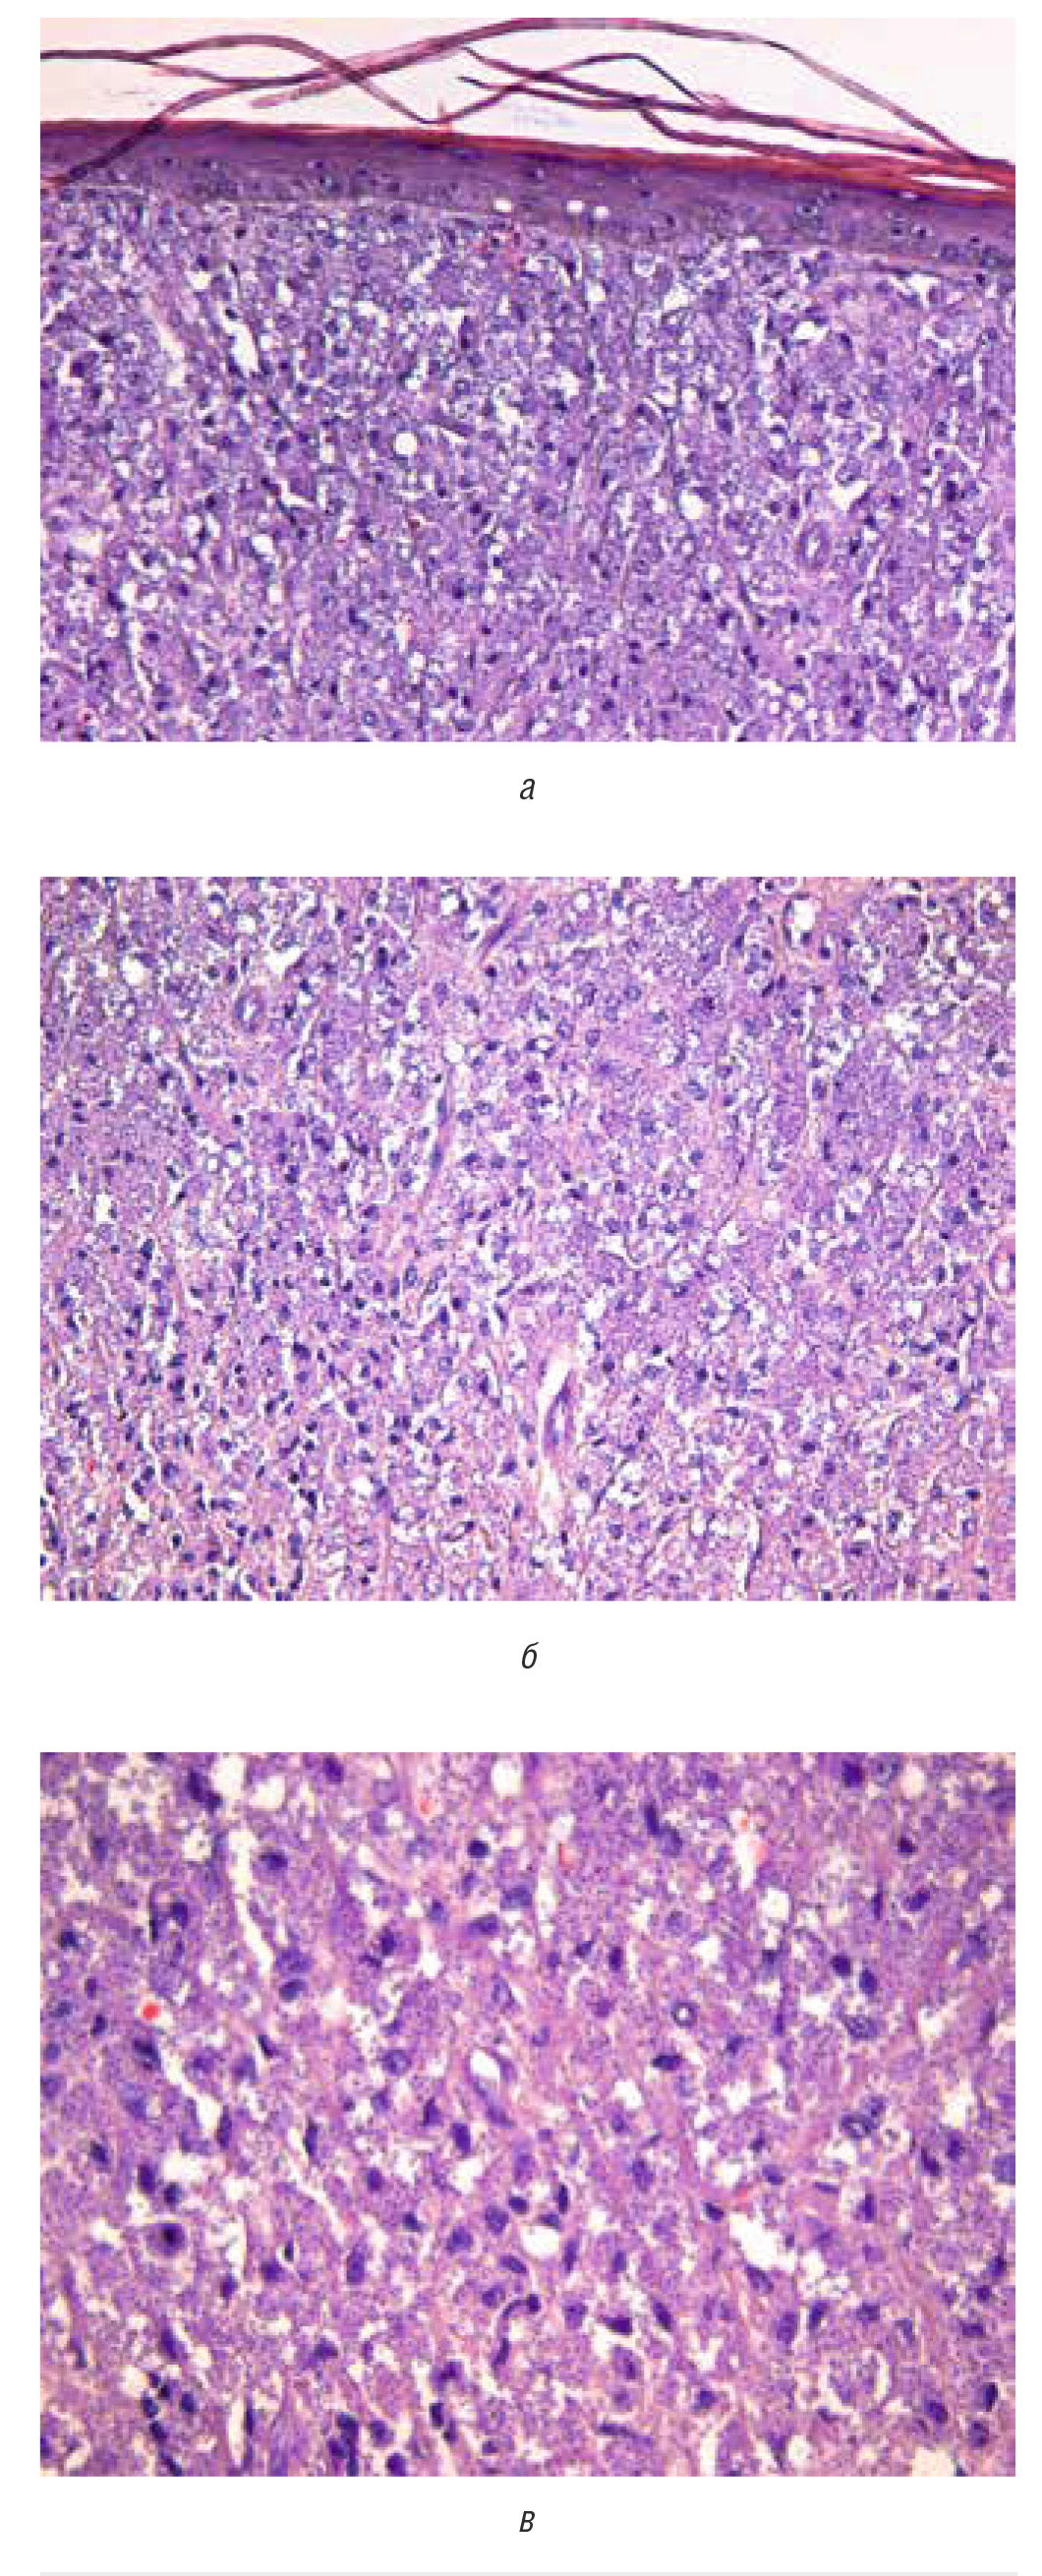

При гистологическом исследовании: дерму субтотально заполняет плотный инфильтрат, представленный крупными гистиоцитами, в цитоплазме которых содержатся множественные паразиты в виде округло-овальных базофильных включений (рис. 6). Также среди инфильтрата присутствует скудное количество лимфоцитов и плазмоцитов. В верхней части дермы инфильтрат располагается диффузно, в нижней трети приобретает нодулярный вид, концентрируясь вокруг волосяных фолликулов и протоков эккринных желез. При окраске по Цилю–Нильсену кислотоустойчивых микобактерий не обнаружено. Заключение: признаков лепры в пределах присланного материала не обнаружено. Выявленные изменения наиболее соответствуют лейшманиозу.

Рис. 6. Гистологическое исследование. Дерму субтотально заполняет плотный инфильтрат, представленный крупными гистиоцитами и макрофагами, в цитоплазме которых содержатся множественные паразиты в виде округло-овальных базофильных включений (а — увеличение ×10, б — увеличение ×20, в — увеличение ×40)